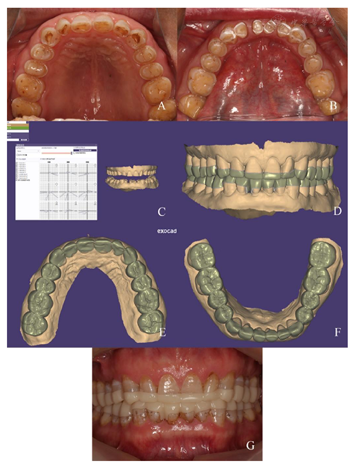

17-47重度磨耗至牙本质深层,探无不适,叩痛(-),未及明显松动,牙龈无明显异常;上颌

垫固位稳定可,正中咬合接触均匀,前伸侧方咬合无干扰,

垫厚度双侧第二磨牙1mm,第一磨牙1.5mm,前牙3mm;双侧颞下颌关节及咀嚼肌区域无压痛,双侧颞下颌关节无弹响,开口度、开口型正常;方圆面型,面部左右对称,双侧咬肌肥厚,面下1/3比例偏低。

17-47重度磨耗至牙本质深层,探无不适,叩痛(-),未及明显松动,牙龈无明显异常,牙髓活力正常;

41可见牙色充填体,X线片示:根充恰填,根尖周病变范围较治疗前缩小。

上颌

垫厚度双侧第二磨牙1mm,第一磨牙1.5mm,前牙3mm;

17-47重度磨耗